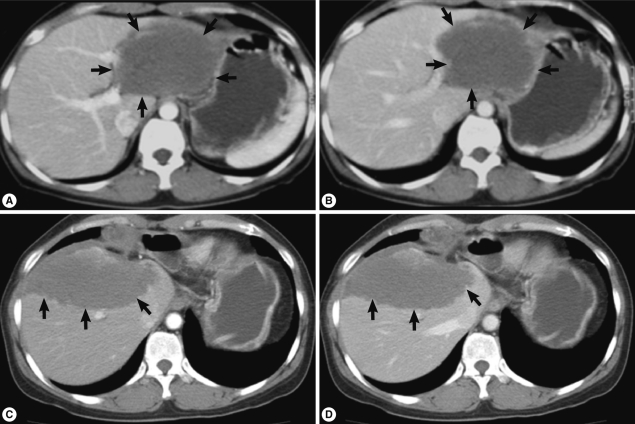

At Dong-A University Hospital, the liver showed an 8 cm sized ill-defined mass with 1.5 cm and 3 cm sized satellite nodules at the left lateral segment of the liver without lymph node enlargement on CT imaging. Contrast enhanced CT scan demonstrated low attenuated mass (Fig. 1A, B) and no or poor enhancement after contrast injection. These radiologic findings suggested an inconclusive hepatic tumor with necrosis. Although non-neoplastic mass was considered, malignancy such as cholangiocarcinoma should be ruled out radiologically. Laboratory data from routine CBC, chemistry, serology, electrolyte profiles, hormone analysis of blood, tumor markers (α-fetoprotein, carcinoembryonic antigen, and CA 19-9), and urine analysis were all within normal limits. To rule out any possibility of malignancy, left hepatectomy was done. During operation, frozen section made by the biopsied hepatic mass revealed necrotizing granulomatous inflammation. The lobectomized liver showed a relatively demarcated mass, 11 cm in greatest dimension and abutted several nodular masses of 1-3 cm in diameter, which showed necrosis on cut surface, grossly. Histologically, extensive coagulation necrosis, granulomas, and dispersed acellular membranous shells within cystic spaces were observed. These gross and histologic findings corresponded with a parasitic infection of the liver, but identification of the specific parasite species was not processed. She was discharged without complications.

During follow-up, on 19 July 2005, a new nodular mass, 4.5×3.0 cm was observed in S5/8 segment of post-hepatectomized liver on CT imaging, and a needle biopsy of the mass showed coagulation necrosis. The hepatic mass was checked to be enlarged to 6.3×4.5 cm and several small nodules in both basal lungs on 7 August 2007. The hepatic mass showed extensive necrosis, and the pulmonary nodules represented calcification and focally impinged air, suggesting calcified granuloma rather than metastatic malignancy. On 7 May 2010, the hepatic mass was more enlarged, up to 10 cm in diameter and right supradiaphragmatic lymph node enlargement was found on contrast enhanced CT scan. Imaging study showed the same features of the previous mass (Fig. 1C, D). On the lung setting of chest CT scan, relatively well defined small nodules were seen in both lower lobes of the lung, suggestive for calcified granulomas, and metastasis, even less likely (Fig. 2). The eosinophilic count was 8.9% (reference value: 0-7%), total IgE was 1,944 kU/L (reference value: 0-200 kU/L), and parasitological studies were all negative for helminths, including Ascaris lumbricoides, Trichuris trichiura, Enterobius vermicularis, hookworms, and protozoa.

AE is rare but fatal. It has a risk of metastasis in advanced stages, usually resulting in secondary lesions in the lung or brain. A fatal outcome may occur in over 95% of untreated patients within a 10-year period following diagnosis [1]. When a slowly growing tumor, visualized by imaging techniques, is detected, a case is verified if at least 2 of the following 4 parameters are fulfilled, according to the WHO recommendations: 1) Typical organ lesions detected by imaging techniques, e.g., abdominal ultrasound, CT, and magnetic resonance imaging, 2) Detection of E. multilocularis specific serum antibodies by serotests, 3) Histopathology compatible with AE, 4) Detection of E. multilocularis nucleic acid in a clinical specimen [2,7]. CT imaging of slow growing and recurred mass in this case displayed ill-defined hypodense mass with poor or no enhancement after contrast injection and no differences on arterial and portal phase, which is characteristic for hepatic AE [8]. During the follow-up period of our case, multiple basal nodules at both lungs appeared, showing pulmonary extension. However, it is sometimes difficult to rule out other parasitic infections, pathologically and clinically, especially in non-endemic areas. Multiple cysts, mostly empty and histologically lamellated membrane along the inner side of the cysts with characteristic PAS (+) stain, are compatible with AE [2,4,8].

Fig. 1

Contrast enhanced abdominal CT scan (A and B, imaging at 1st operation; C and D, imaging at 2nd operation; A and C, arterial phase; B and D, portal phase). CT reveals a low attenuated huge mass (arrows) with little difference between arterial and portal phases.

Fig. 1 Contrast enhanced abdominal CT scan (A and B, imaging at 1st operation; C and D, imaging at 2nd operation; A and C, arterial phase; B and D, portal phase). CT reveals a low attenuated huge mass (arrows) with little difference between arterial and portal phases.